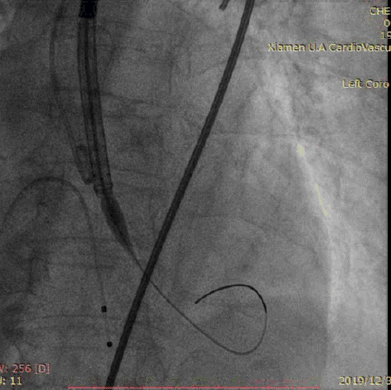

瓣膜释放后造影